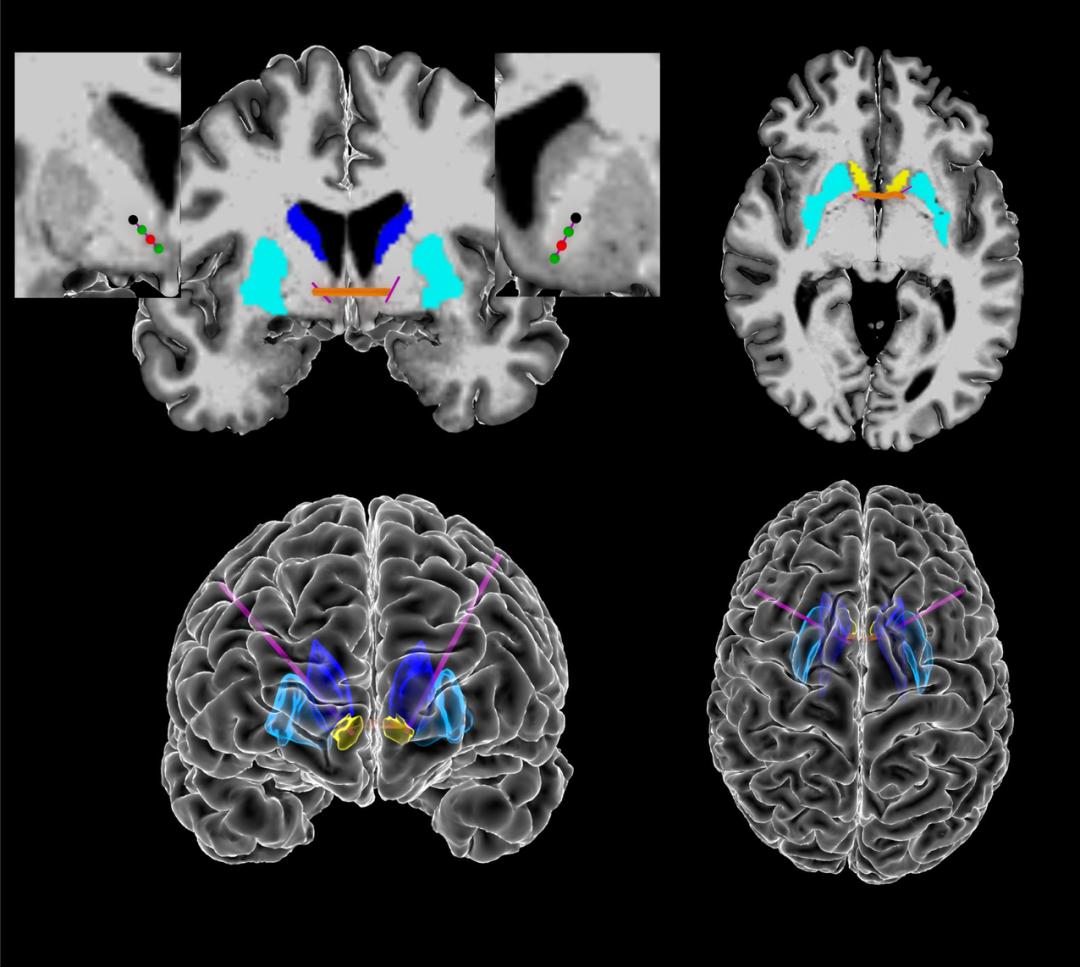

图 | 颅内电生理数据的采集(来源:Nature)

为此,Borton 教授带领的研究团队招募了 5 名接受深部脑刺激治疗的重度强迫症患者进行试验,收集强迫症患者的脑电波活动,同时利用视频记录患者的生活和行为,并利用人工智能评估患者各种微妙的情绪变化,并与脑电波活动相匹配。

结果发现, 与以往的经验不同,强迫症的大脑信号不仅仅来自于大脑腹侧内囊/腹侧纹状体 ,也来自于大脑皮质-纹状体-丘脑-皮质环路。 除了脑电波信号,研究人员还收集了一套强迫症患者行为的生物标志物,包括面部表情和身体运动。通过人工智能,他们发现这些行为和特征与大脑内部信号变化密切相关。

图 | 大脑深部刺激的作用示意(来源:Nature)

同时,研究人员证明,当患者出现这些强迫症标准,无论是大脑信号还是行为标志时进行深部脑刺激可以显著改善患者的强迫症状。